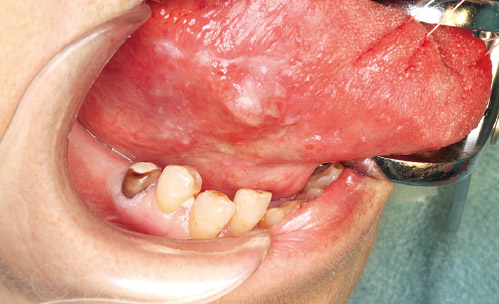

右側縁に軽度な隆起性病変と周囲の白板状変化をともなった病変を認める。

視診で確認するよりも広範な不染域を伴っていた。

外方発育型であり深部の切除は比較的浅く留めることができた。